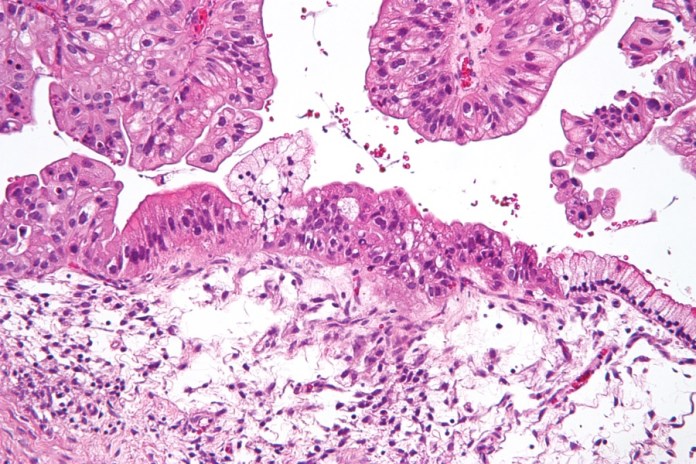

Currently, pathologists perform diagnoses for most diseases through examining cells and tissues that are drawn from the body during a biopsy in a bid to identify abnormalities. According to a statement by the company, Nucleai’s technology is made to reduce patients’ wait time for a diagnosis, reduce errors, and enhance the efficiency of a pathologist.

According to Veidman’s remarks, Nucleai recently presented the results of its artificial intelligence technology to several pathologists who gave enthusiastic responses. Similar to a pathologist’s work, which revolves around detecting patterns, Nucleai’s software is also designed to identify cell patterns from an image and then alert or inform the pathologist. By doing so, the software makes the work of pathologists more accurate and fast.

Aside from its artificial intelligence technology for pathologists, the company has come up with solutions for breast, prostate and gastrointestinal-related complications. In addition, Nucleai plans to utilize its finances to hire experienced researchers in machine learning in a bid to expedite development.